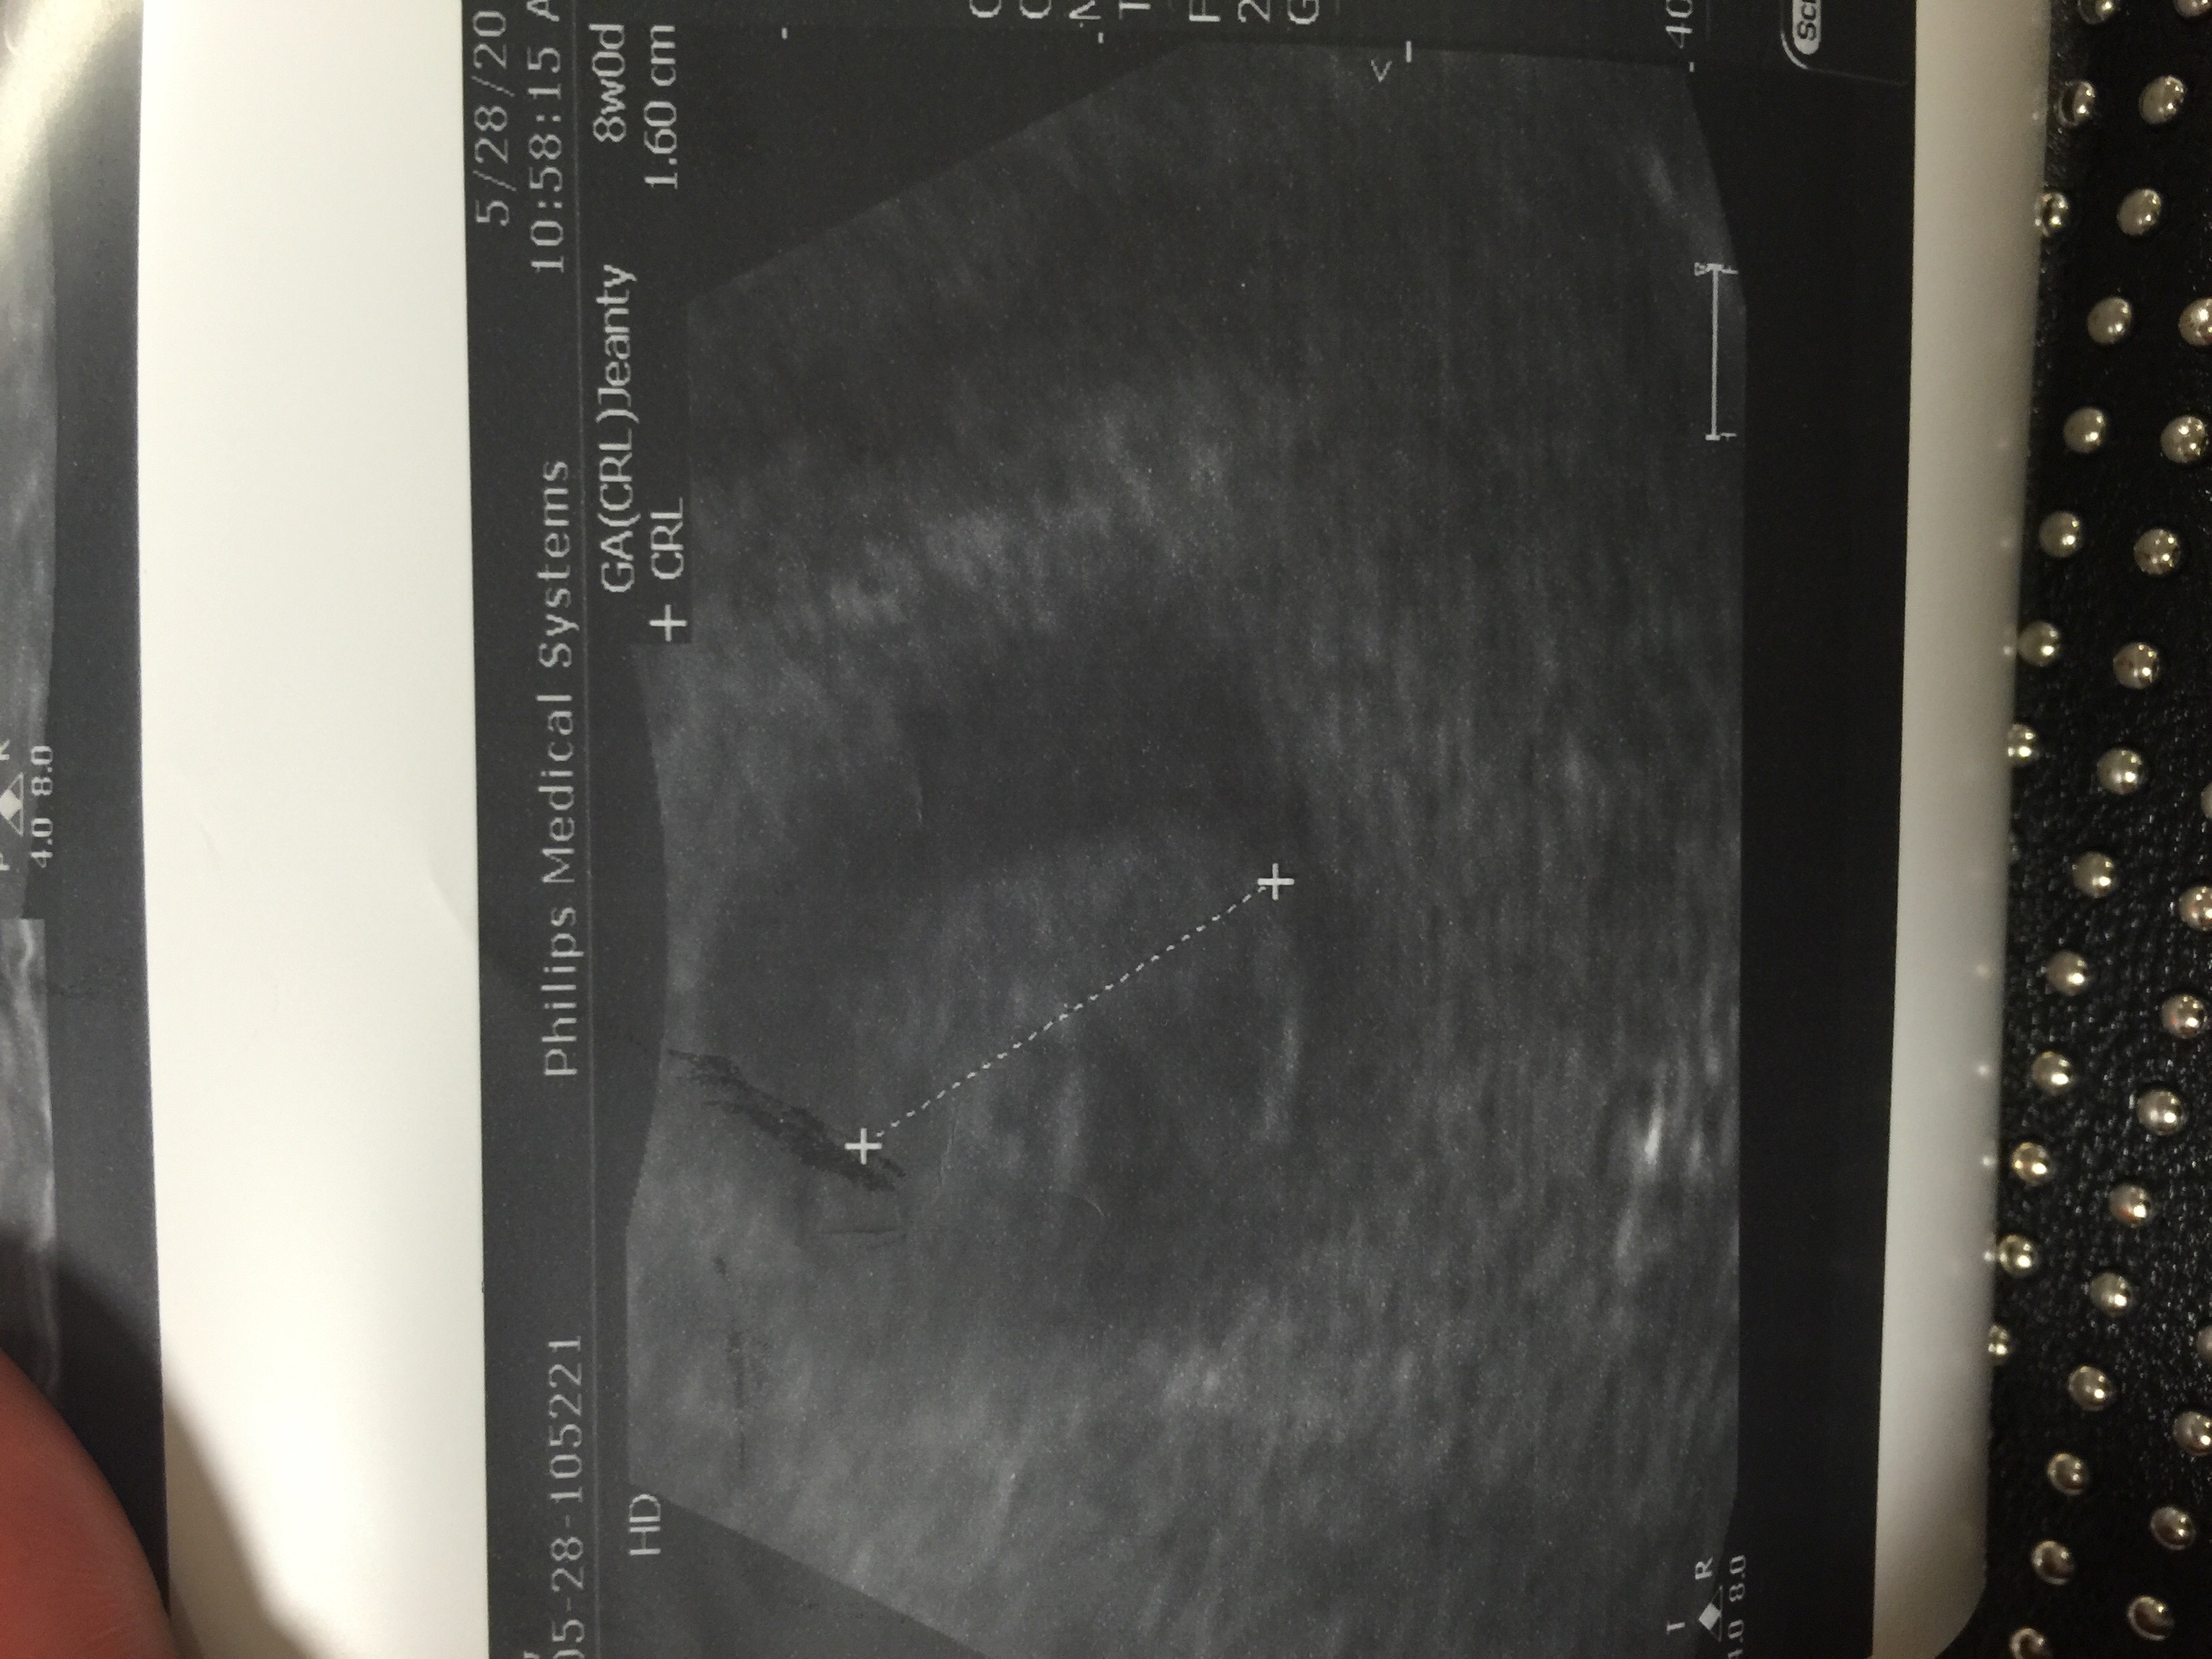

We told everyone today, after my 7 week ultrasound. I'm aware that things could happen but I know the same people that congratulate me now will be my support system if things go wrong!

We had our 8 week appt today and we have decided on telling everyone on Father's Day. I will be just shy of 12 weeks then. Appt went great today our little bean had an active heart rate of 160. We are so excited and hope we have a happy and healthy rest of this pregnancy